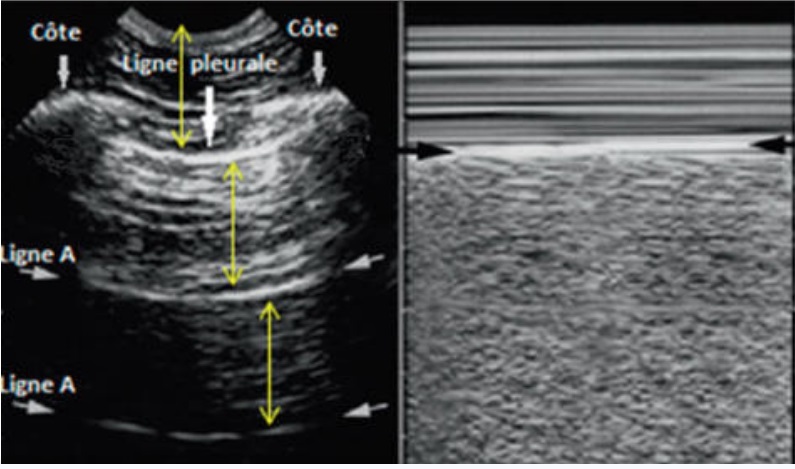

Image echographique normale de

la pleve du poumon en presence sous forme une bande

hyperechogene . Sur image echo en mode TM à droite ,

la ligne pleural hyperechogene entre paroi

thoracique et le poumon se donne de image en " signe

du bord de mer " ( fleche noire ) . |